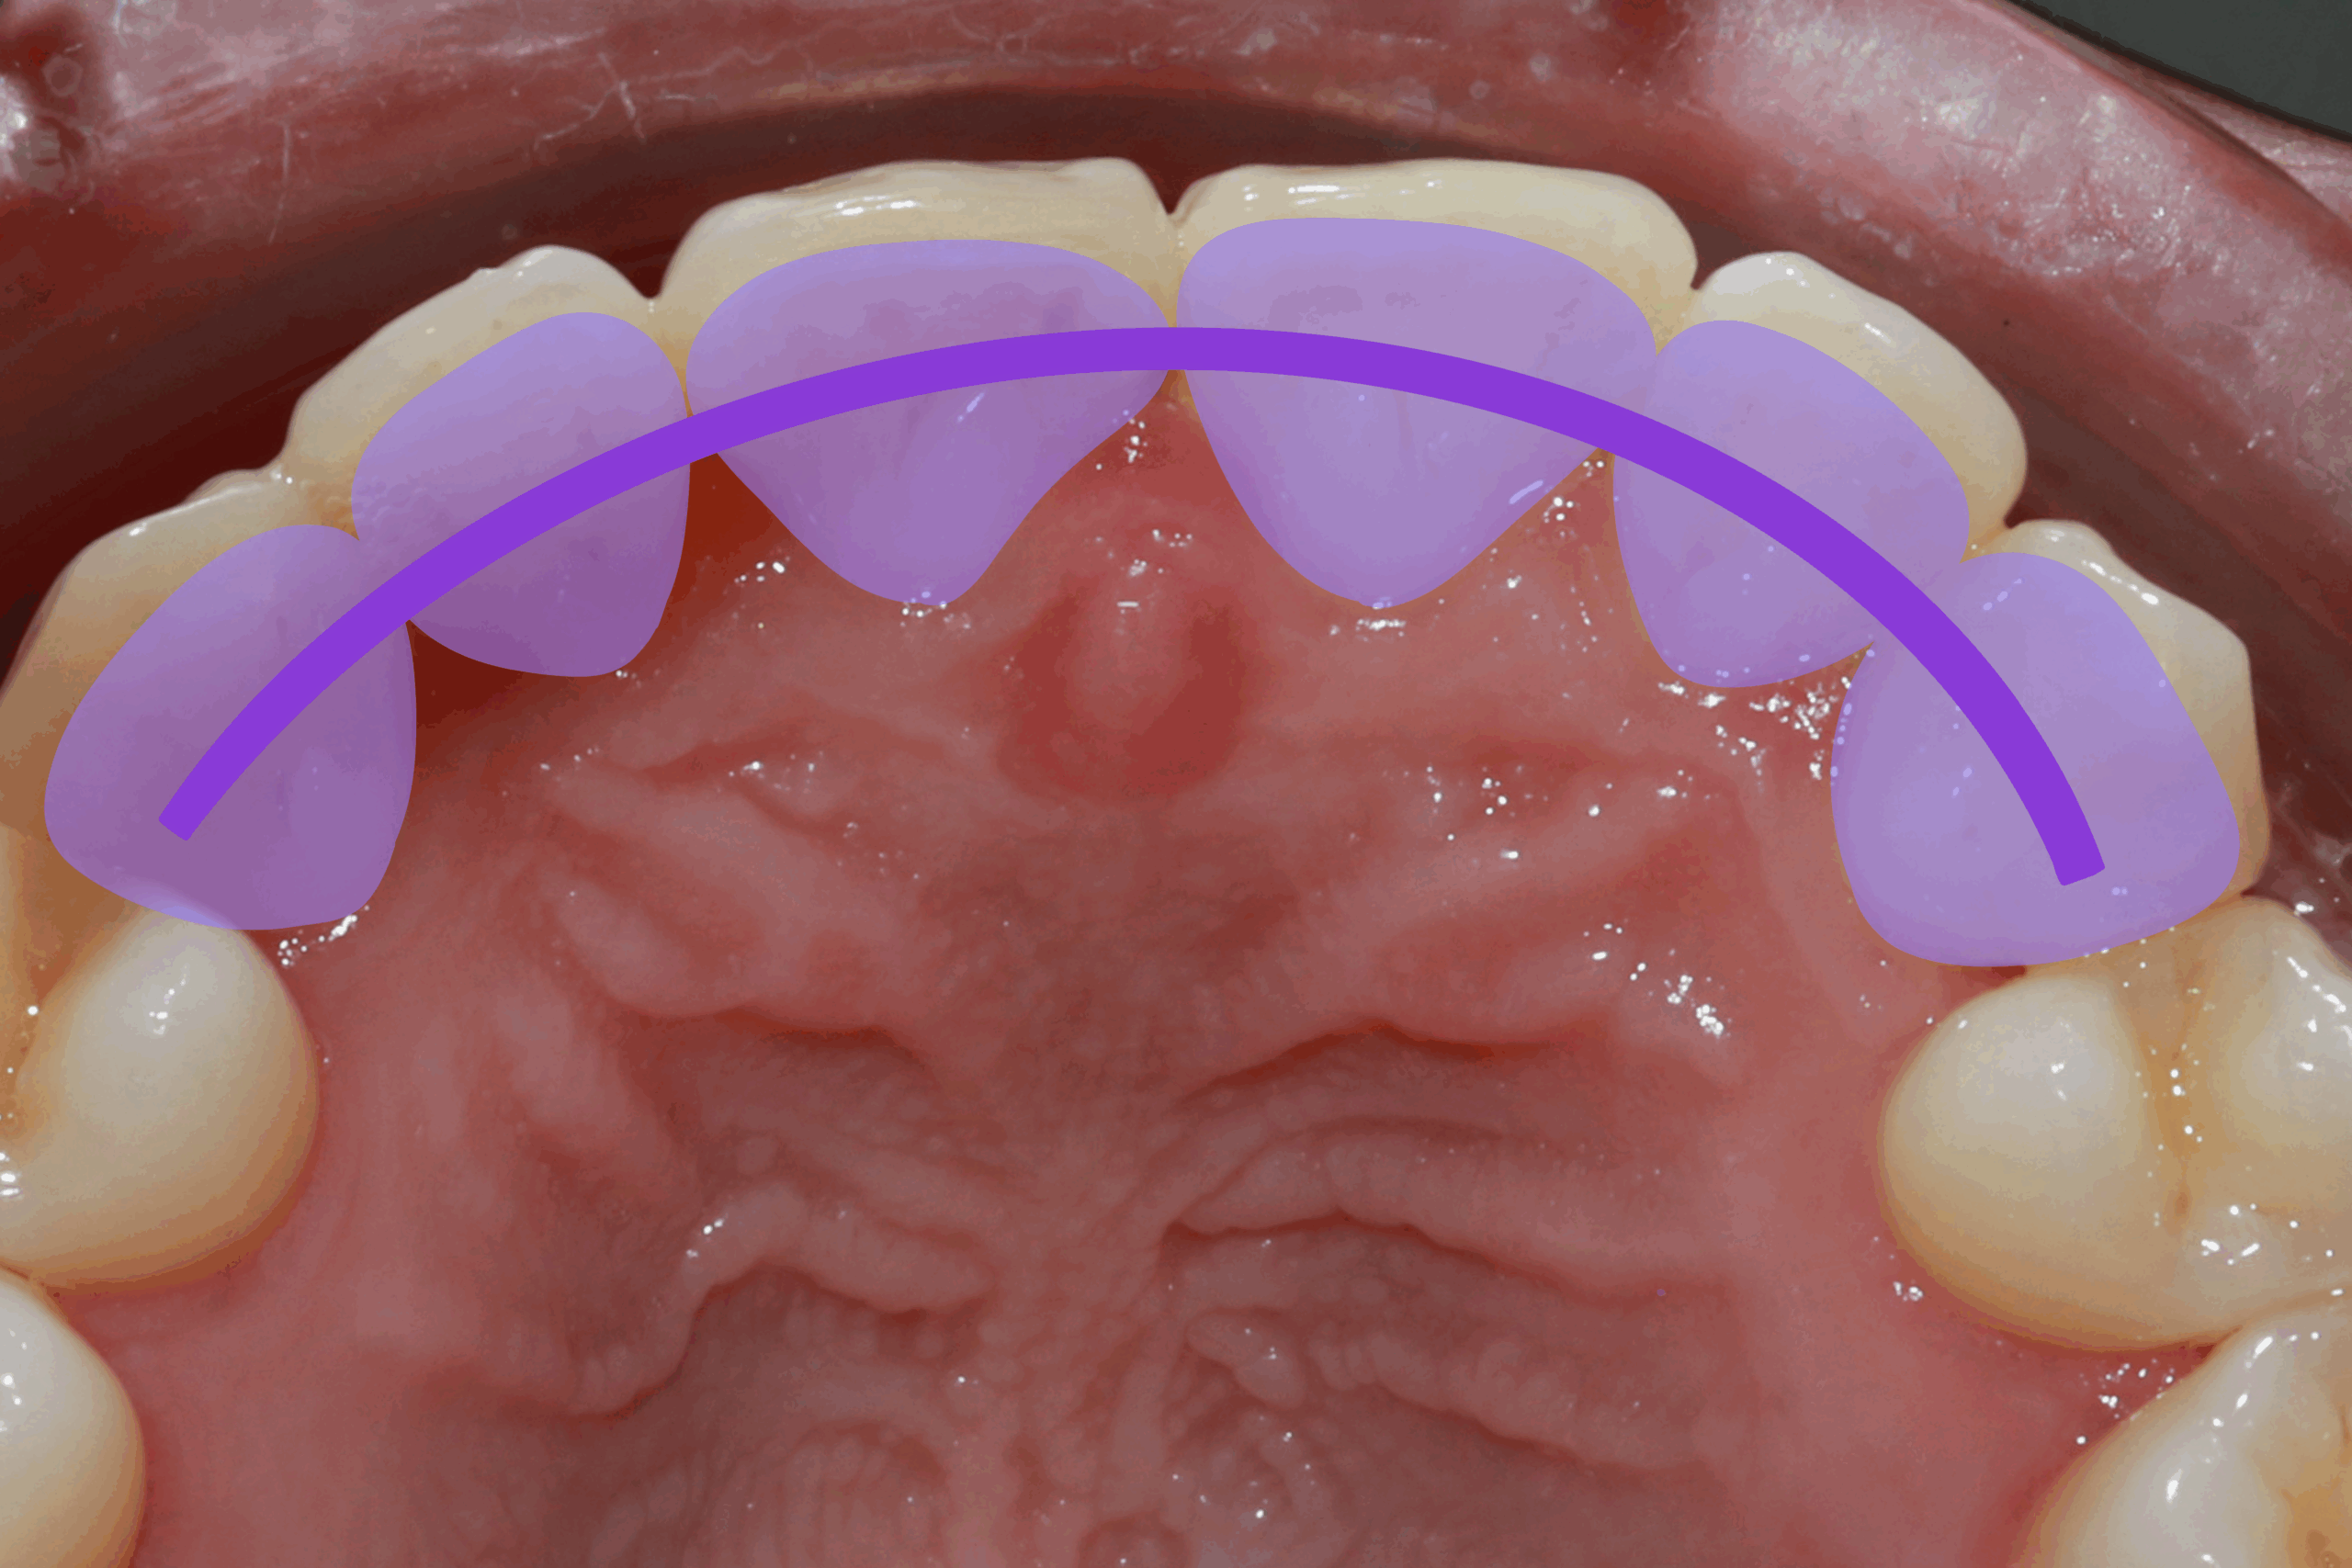

La contention fibrée collée est une technique qui consiste à poser une fibre de verre pré-impregniée sur la face interne des dents allant en général de canine à canine. Elle est recouverte d’un composite de stratification de haute densité.

Ce système permet la stabilisation des dents tout en maintenant un environnement parodontal sain. Elle peut en fonction de la situation être posée en haut ou/et en bas.